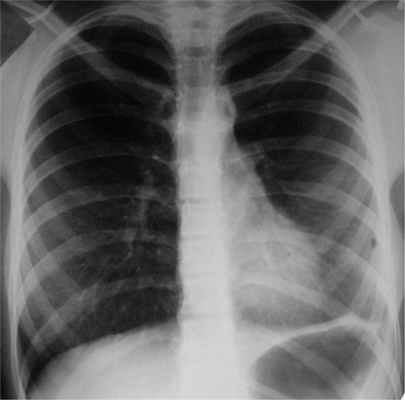

При обследовании через 3 года после операции самочувствие хорошее, физическое развитие соответствует возрасту. Одышки нет, занимается спортивной гимнастикой. Деформации грудной клетки и сколиоза, наблюдавшихся перед операцией, нет. При исследовании функции легких вентиляционная способность легких нормализовалась (жизненная емкость легких 102%, объем форсированного выдоха за 1-ю секунду 105%). Обострений туберкулеза за 3 года не было, в мокроте при всех исследованиях МБТ не обнаружены. При обзорной рентгенографии (рис. 5) Рис. 5. Обзорная рентгенограмма органов грудной клетки больной Г. через 3 года после ВАТС-плеврэктомии с декортикацией левого легкого по поводу хронической туберкулезной эмпиемы плевры. Легкие хорошо пневматизированы, признаков обострения туберкулеза нет. легкие хорошо пневматизированы, признаков обострения туберкулеза нет.